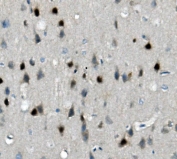

IHC staining of FFPE rat brain with Calbindin 2 antibody. HIER: boil tissue sections in pH8 EDTA for 20 min and allow to cool before testing.